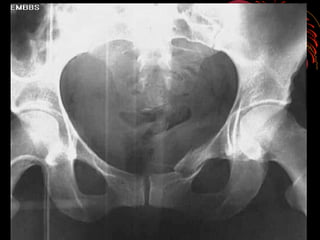

RADIOLOGÍA

• LA IMAGENOLOGIA NO DEBE RETRASAR MANEJO

INICIAL

• TIPO DE IMÁGENES ESTA DADO POR MECANISMO,

GRAVEDAD Y CAPACIDAD DEL CENTRO

• PARTIR DE UNA RX. A.P. PARA DIAGNÓSTICO

• COMPLEMENTARIS : 60°”E”-30°”S” Y OBLICUAS

RADIOLOGÍA • LA IMAGENOLOGIANO DEBE RETRASAR MANEJO INICIAL • TIPO DE IMÁGENES ESTA DADO POR MECANISMO, GRAVEDAD Y CAPACIDAD DEL CENTRO • PARTIR DE UNA RX. A.P. PARA DIAGNÓSTICO • COMPLEMENTARIS : 60°”E”-30°”S” Y OBLICUAS • TAC : Herramienta de elección en fx. de pelvis permite evaluar el compromiso óseo, fragmentario, grados de desplazamiento, compromisos abdominopélvicos y diferenciar hematomas retro e intra abdominales • Uretrocistograma en caso de hematuria franca • Angiografía :evidencia de hematom retroperitoneal y perdida de mas de 4 unidades de GR